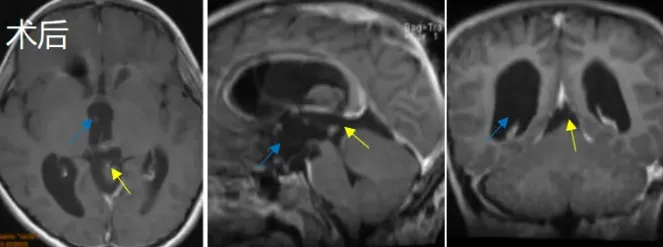

术后

术后第一天晃晃保持清醒状态,在ICU观察两天后情况良好,无明显并发症,也没有出现小脑肿胀,顺利出院。孩子术前的各种症状慢慢消失,恢复了正常机体功能,最近复查时肿瘤也并未复发。